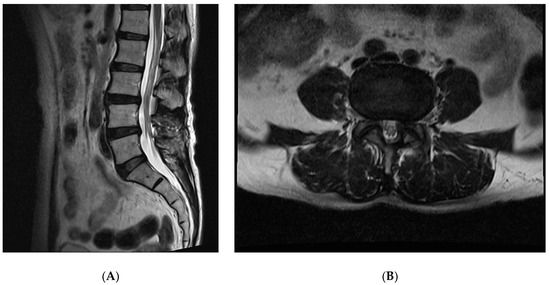

Although lumbar synovial cysts (LSCs) are frequently described in the literature, they are a relatively uncommon cause of low back and radicular leg pain. Furthermore, their spontaneous resolution is an even rarer event. The standard treatment of the lumbar synovial cyst is surgical [...] Read more.

Although lumbar synovial cysts (LSCs) are frequently described in the literature, they are a relatively uncommon cause of low back and radicular leg pain. Furthermore, their spontaneous resolution is an even rarer event. The standard treatment of the lumbar synovial cyst is surgical excision. Spontaneous resolution in the literature is a sporadic event. In our experience, we have had two cases where the lumbar synovial cyst disappeared spontaneously. To date, only nine cases of spontaneous resolution of synovial cysts have been documented in the literature. In this discussion, we highlight a pathology that typically suggests surgical intervention, yet conservative treatment can be a viable alternative. We present two cases of large synovial cysts that were initially scheduled for surgery but ultimately resolved spontaneously without any treatment. While the spontaneous resolution of lumbar synovial cysts is extremely rare, conservative strategies are an option that should not be overlooked. Our cases contribute to the growing body of evidence on the spontaneous regression of symptomatic LSC, potentially enhancing the understanding of the disease’s natural progression in the future. Full article

Show Figures

Figure 1